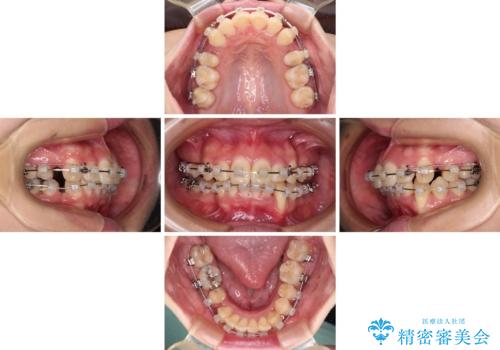

出っ歯を治したい ワイヤー装置での抜歯矯正で劇的変化!

- 口元がひどく突出するくらいの上顎前突を気にして来院された患者様です。

舌の突出癖が顕著で、上顎歯列は完全なV字型となっている状態でした。

下顎歯列にも八重歯があり、上下左右の第一小臼歯4本を抜歯して、ワイヤー装置にて矯正治療を行うこととしました。

どこまで口元の突出感を改善できるのか不安でしたが、舌のトレーニングをしっかりと行ってくださり、我々も驚くほど劇的に改善することができました。